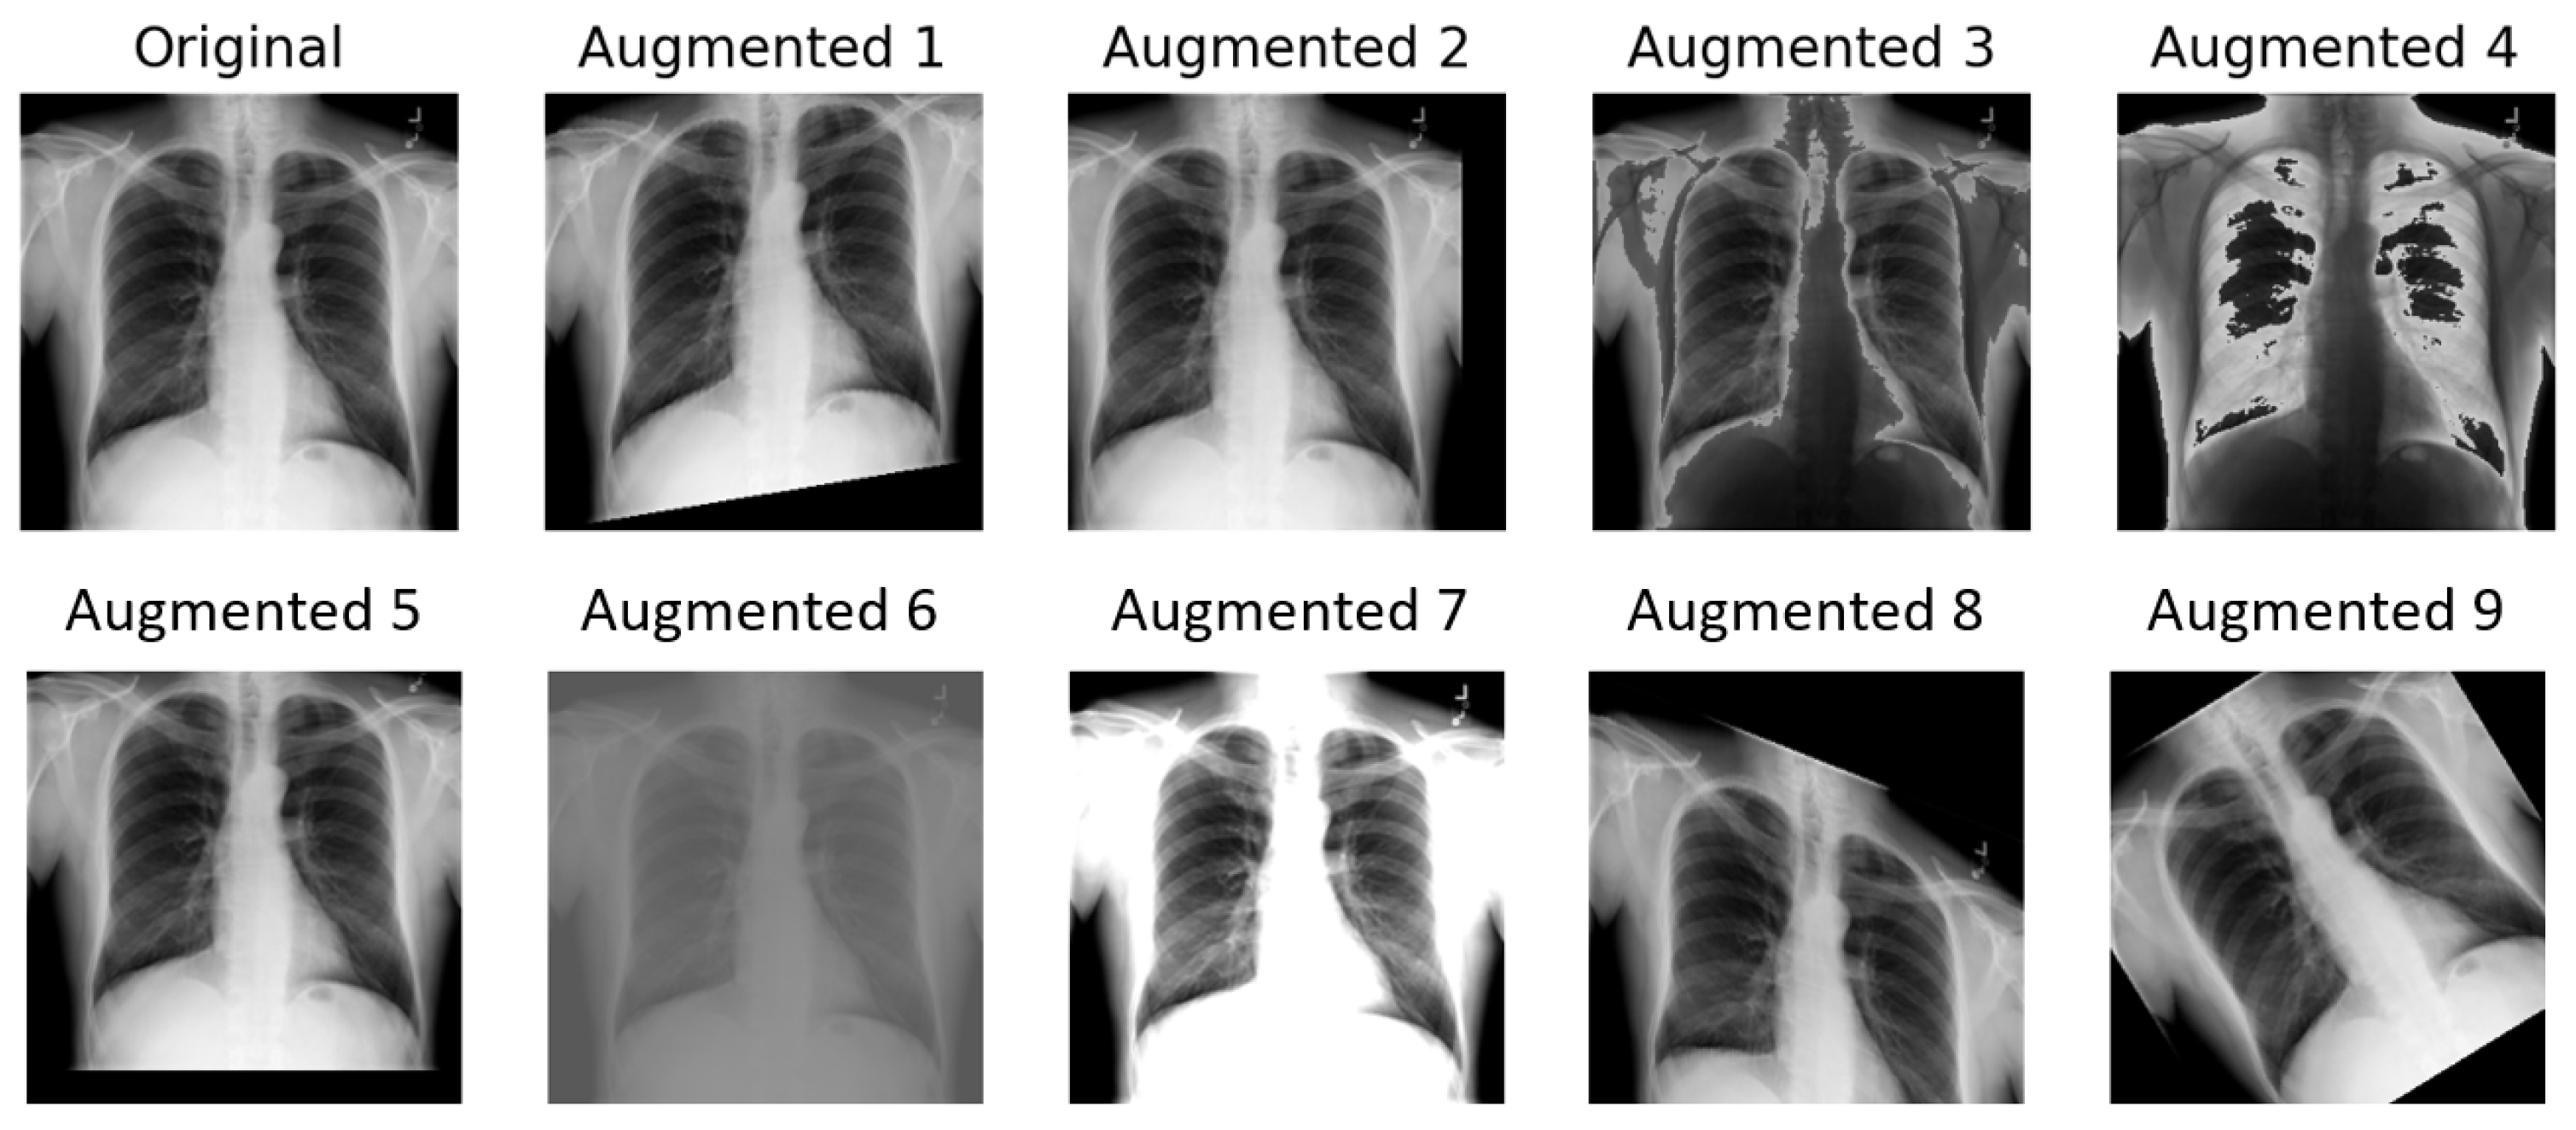

The implementation of TrivialAugment employed in this paper is based on [13]. It uses the same augmentation space as the original paper, described in Algorithm 1. For the training image, only one operation is chosen each time. The choice of operation within the augmentation space is completely random. An illustration of TrivialAugment applied nine times on a chest X-ray sample is presented in Figure 5.

Figure 2. An example of TrivialAugment augmentation applied four times.